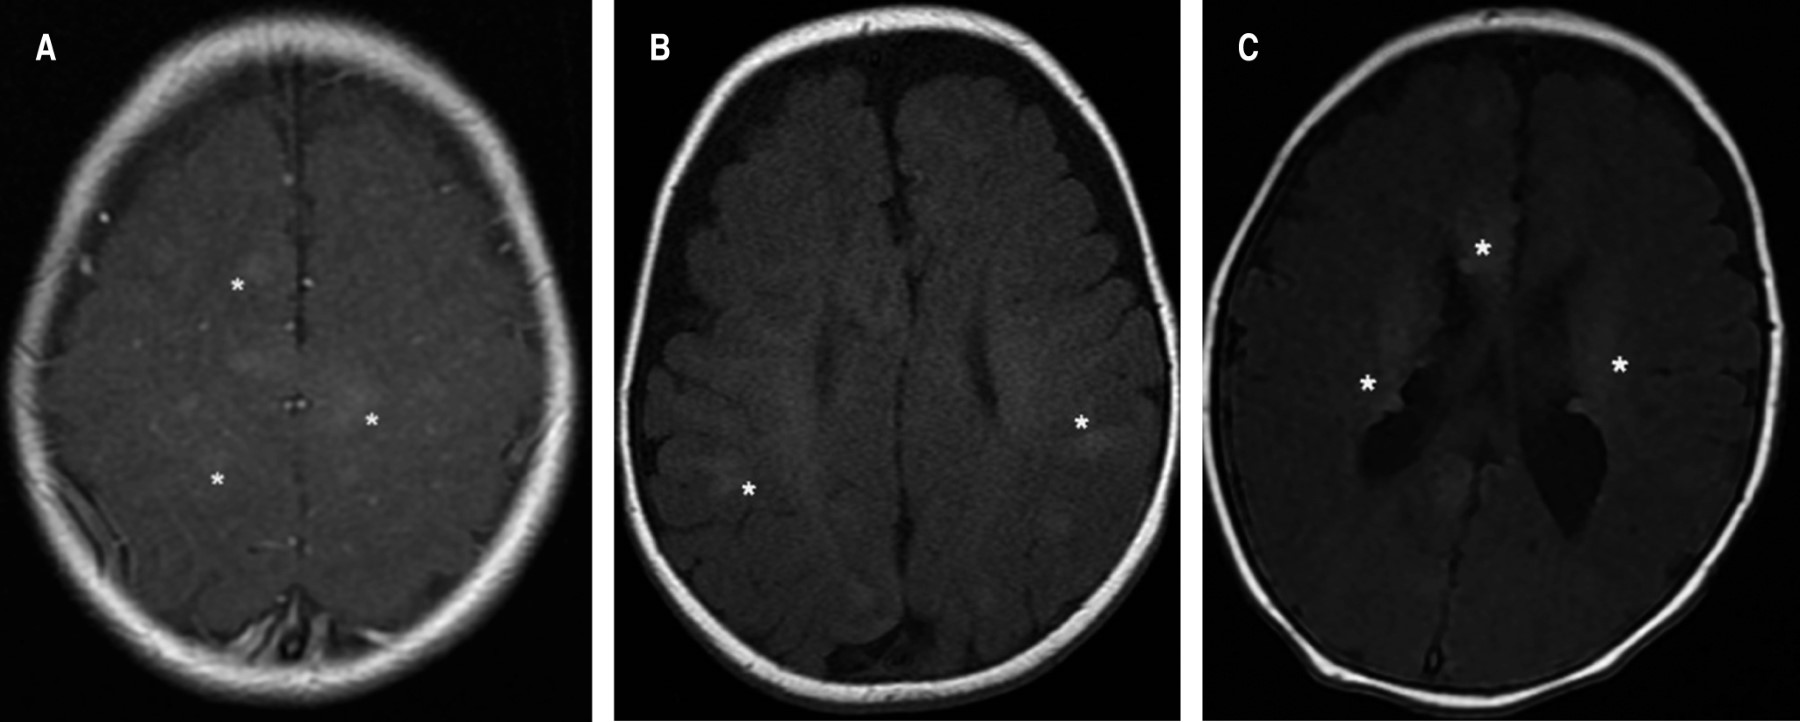

Las manifestaciones neurológicas son la principal causa de morbilidad y mortalidad en pacientes con CET, incluyendo las displasias corticales, las cuales se definen como trastornos de la migración neuronal durante el desarrollo embrionario. De los pacientes aquí reportados, la mayoría presentó hamartomas glioneuronales corticales, nódulos subependimarios o líneas de migración radial en la sustancia blanca (Figura 2).20

Con respecto al SEGA, los presentan de 5-20% de los pacientes con CET; son tumores benignos, de crecimiento lento que surgen en el área periventricular.6,21 Su detección suele ser después de la segunda década de la vida, causando compromiso neurológico grave, incluyendo hidrocefalia obstructiva, por lo cual se recomienda realizar estudios de imagen de resonancia magnética (IRM) de manera anual o cada tres años; ninguno de los pacientes en esta serie lo presentaron. Por otro lado, con IRM también es posible encontrar lesiones en la sustancia blanca como nódulos, quistes y áreas de gliosis e hipomielinización.22